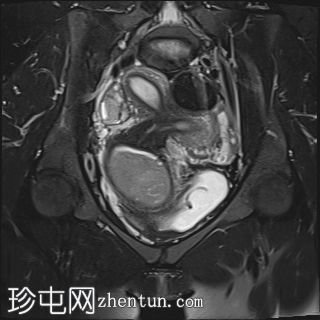

盆腔增强 MRI 检查增强了我们对 CT 扫描中发现的病变的理解。右肾发育不全,左肾肥大伴肾积水,双子宫完整,阴道隔膜,发育不全侧阴道积血。

双侧卵巢均有多个功能性囊肿,右侧卵巢可见黄体囊肿。

道格拉斯囊内可见少量游离液体。